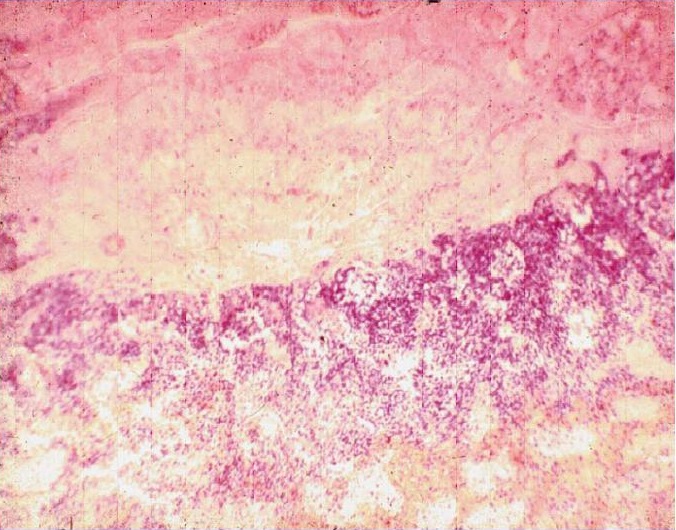

Ишемический инфаркт почки с демаркационной линией (гистологический препарат)